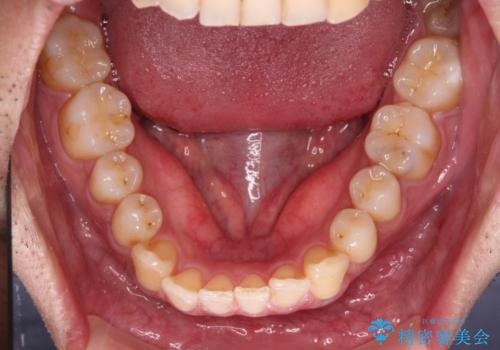

- 上下前歯のデコボコを気にして来院された患者様です。

口元の突出感や奥歯の咬み合わせに問題がなかったため、インビザラインの廉価版パッケージを用いるか上下ワイヤー装置での部分矯正を提案しました。

インビザライン廉価版パッケージの方が価格としては安価でしたが、日々の自己管理が煩雑であるとのことで、ワイヤー装置にて矯正治療を行うこととしました。